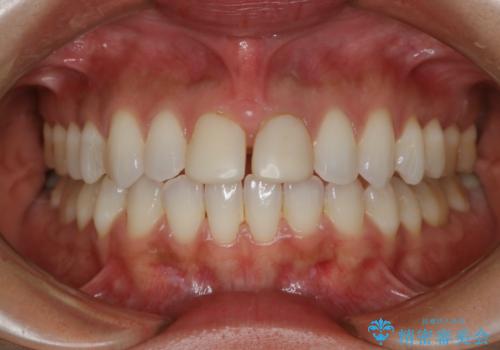

すきっ歯を治したい。インビザライン・ライトによる矯正治療

- 正中離開を気にされて来院された患者様です。

インビザラインでの治療を希望され、正中離開のみ治したいとのことだったので、インビザライン・ライト(片顎)での治療を選択しました。